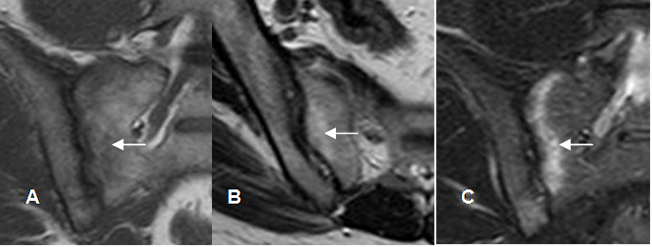

Fig 12. Sacroileitis Subaguda.

A: Rx Pelvis AP. Esclerosis en el componente iliaco derecho.

B: RM T1 coronal y C: RM T2 axial. Osteitis de los componentes sacro e iliaco, hiperintenso en ambas secuencias, por evolución subaguda. (Flechas).